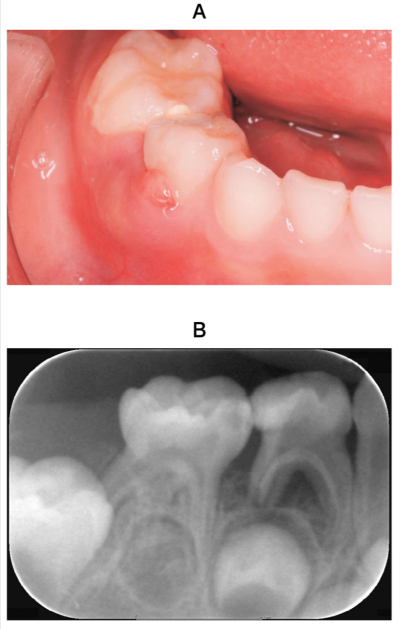

5歳の女児。下顎右側第一乳臼歯部歯肉の発赤と腫脹を主訴として来院した。自発痛はないが、D頰側歯肉の圧痛を認める。初診時の口腔内写真とエックス線画像を別に示す。適切な対応はどれか。1つ選べ。